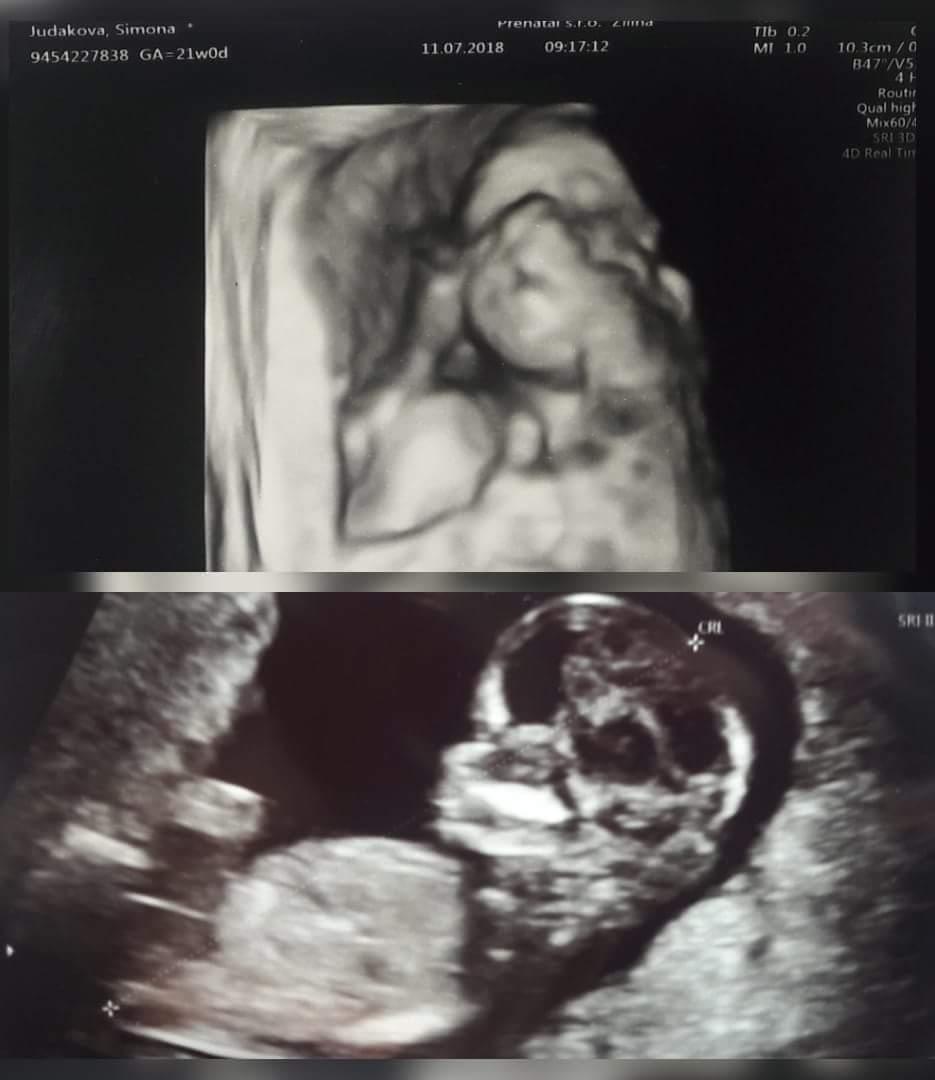

Ja si to užívam velmi od začiatku je všetko ako má byť ani mi nebolo zle, takže všetko super dúfam že to tak pôjde aj ďalej 😊 Len toto teplo ma teraz ničí je to dosť ťažké v takých teplotách už aby bol november 😍